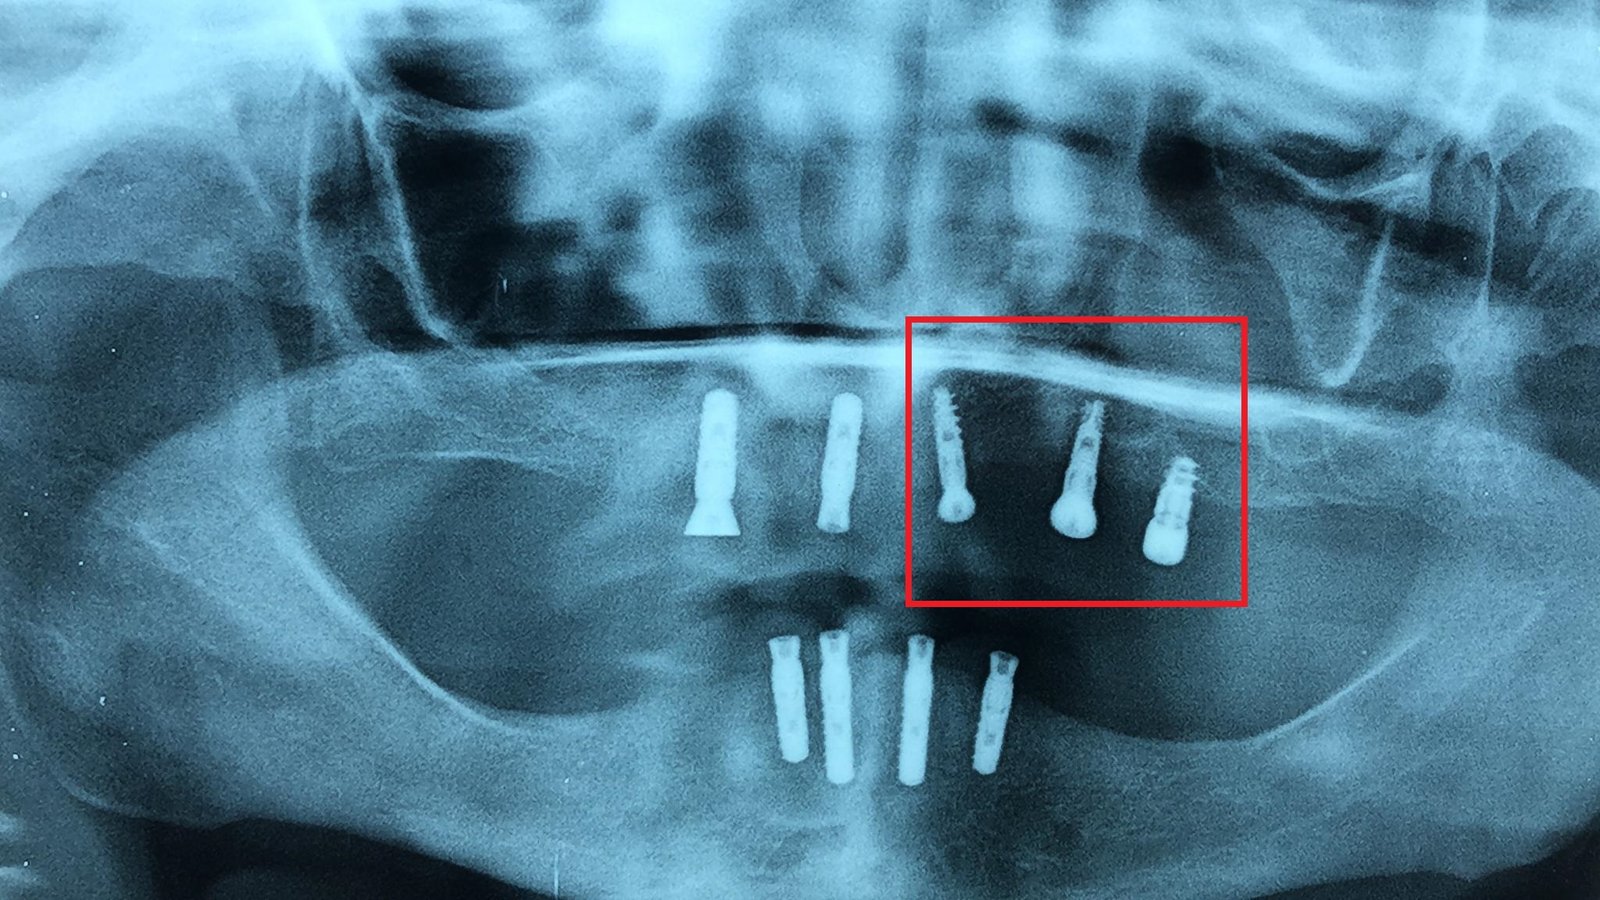

Buenas tardes, Podríais decirme qué implantes son los que están en posición *21/25/27*. muchas gracias, de antemano! Atte: Máximo.

Buenas! Podríais decirme qué implantes son los que están en posición #35.36?? Muchas gracias de antemano!!

Necesito rehabilitar este tercer cuadrante, usando el implante posterior, que no sé cual es, y con respecto a los otros dos, tengo dudas sobre si rescatar el medio y dejar [...]

Buenas tardes. Me encantaría que me ayudaseis con este caso. Es una paciente que viene de dos clínicas diferentes , la parte superior se la hizo en una y la [...]

Hola a todos, se puso los implantes hace años en granada y quiere cambiarse las híbridas. Gracias!

Buenas: Me ha llegado a consulta esta paciente, la cual se coloco los implantes en Andorra hace bastante tiempo. Según mi protesico los implantes corresponden a 3i, en uno de [...]